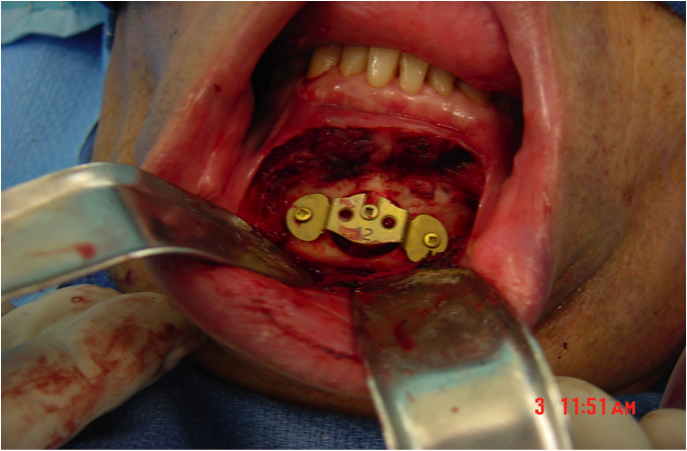

This procedure places tension on the tongue, limiting the posterior from shifting during sleep. The procedure starts with a small incision made inside the lower lip. Then, the surgeon moves away all the soft tissue to expose the lower jaw. Small rectangular cuts are then made in the lower jaw directly in front of the lower front teeth. This area attached to the genioglossus muscle is then moved forward and turned slightly. To hold this bone fragment in place, the surgeon puts in a titanium screw to immobilize it.

The photos on this website are from real surgeries performed by Dr. Ulloa. Due to the

graphic nature of the images and content, viewer discretion is advised.